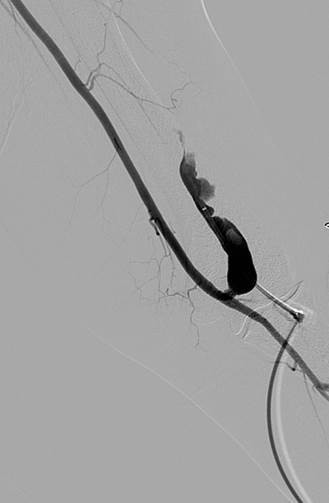

Thrombectomy of occlusion of left brachiocephalic fistula

Fistulogram demonstrating thrombotic occlusion of a left brachiocephalic AV fistula (Note: arterial reflux of contrast).

Post 1st pass with AngioJet DVX Catheter (no thrombolytics used).

Post 2nd pass with DVX Catheter and balloon angioplasty of underlying stenosis. No impedance to forward flow in AVF.

Once forward flow is established and stenosis treated, the residual thrombus should resolve.